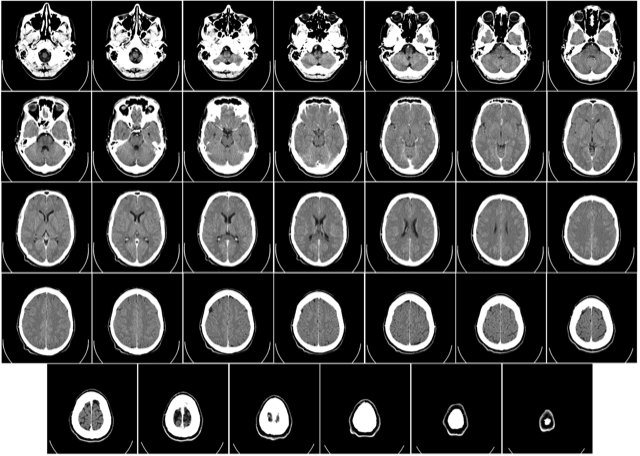

Negli ultimi anni il campo medico e biomedicale ha subito forti cambiamenti legati all’avanzamento delle tecnologie, ma soprattutto alla consapevolezza della necessità di adottare nuovi metodi per l’analisi dei dati prodotti quotidianamente in ospedale. Quello a cui si sta assistendo oggi è un’apertura verso l’utilizzo di tecnologie innovative sia in campo genomico che nell’analisi di immagini medicali e più in generale dei vari dati prodotti. Questa nuova spinta è fortemente legata all’accettazione di soluzioni basate su Intelligenza Artificiale, che al giorno oggi ha una forte trazione su molti campi applicativi. Negli ultimi anni, infatti, stiamo assistendo alla nascita di molteplici applicazioni che, sfruttando tecniche di Machine Learning, analizzano immagini supportando i medici nel processo diagnostico. Sempre più spesso infatti si trovano soluzioni tecnologiche che si stanno sperimentando anche in sala operatoria grazie all’uso di realtà virtuale, robot chirurgici e analisi di immagini real-time a supporto degli interventi chirurgi.

In questo ambito, ad oggi al NECSTLab stiamo lavorando allo sviluppo di tool di analisi di immagini per creare soluzioni che supportino gli addetti del settore nel loro lavoro, sfruttando al massimo i dati prodotti da diversi esami che in un ospedale vengono fatti con cadenza quotidiana. Questo tipo d’analisi però spesso richiedono lunghi tempi di calcolo e per questa ragione, sfruttando le diverse conoscenze all’interno del laboratorio, si stanno esplorando diversi approcci di accelerazione di alcuni degli algoritmi utilizzati.